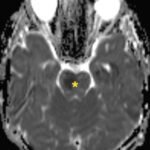

There is a growing body of literature and scientific discovery on pediatric autoimmune encephalitides. This is a heterogenous group of neuroinflammatory conditions leading to often perplexing acute and progressive neurologic and/or neuropsychiatric symptoms. This report demonstrates the evaluation and management of an adolescent with myelin-oligodendrocyte glycoprotein (MOG) antibody-associated fulminant acute disseminated encephalomyelitis (ADEM) in the context of current literature. The featured magnetic resonance imaging uniquely highlights progressive central nervous system lesions detected over the course of the first week of disease.